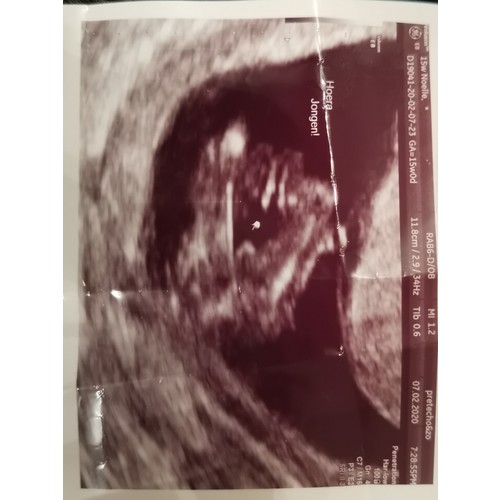

Ik zie geen roze aan de binnenkant? Wel een beetje bruin en donker rood van de taart vulling (chocolademousse en aardbeienjam). Maar volgens mij is hij verder overduidelijk blauw. We hebben de bekendmaking overigens niet gedaan middels de taart maar met een gender reveal ballon en confettipoppers. Ook daarvan was de inhoud blauw. 馃槉 En dat kan ook niet anders want in de envelop die we daarna zelf dus ook hebben opengemaakt zat een echofoto met het geslacht en "hoera, jongen" 馃挋